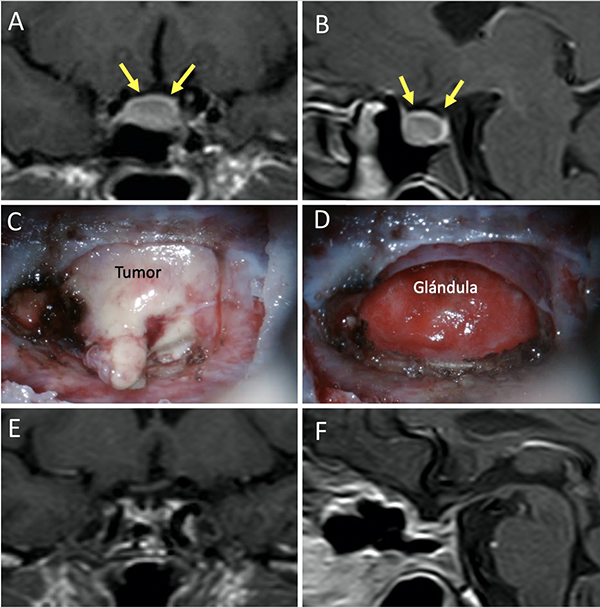

Una clasificación clásica de los adenomas es según su tamaño. Se los clasifica en microadenoma <10 mm (fig. 2), macroadenoma >10 mm (fig. 3), y adenoma gigante > 30 mm (fig. 4). Esta clasificación es importante ya que los índices de remisión están ligados al tamaño del adenoma y también su recidiva.12

Figura 2: Microadenoma. A-B: RM preoperatoria; C-D: RM postoperatoria.